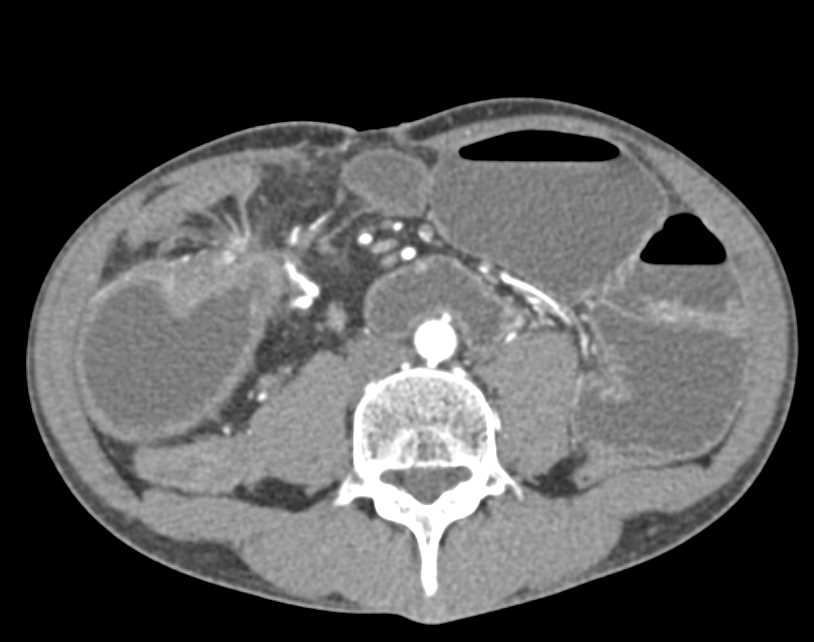

Pneumatosis Small Bowel c/w Ischemic Bowel vs Crohn's